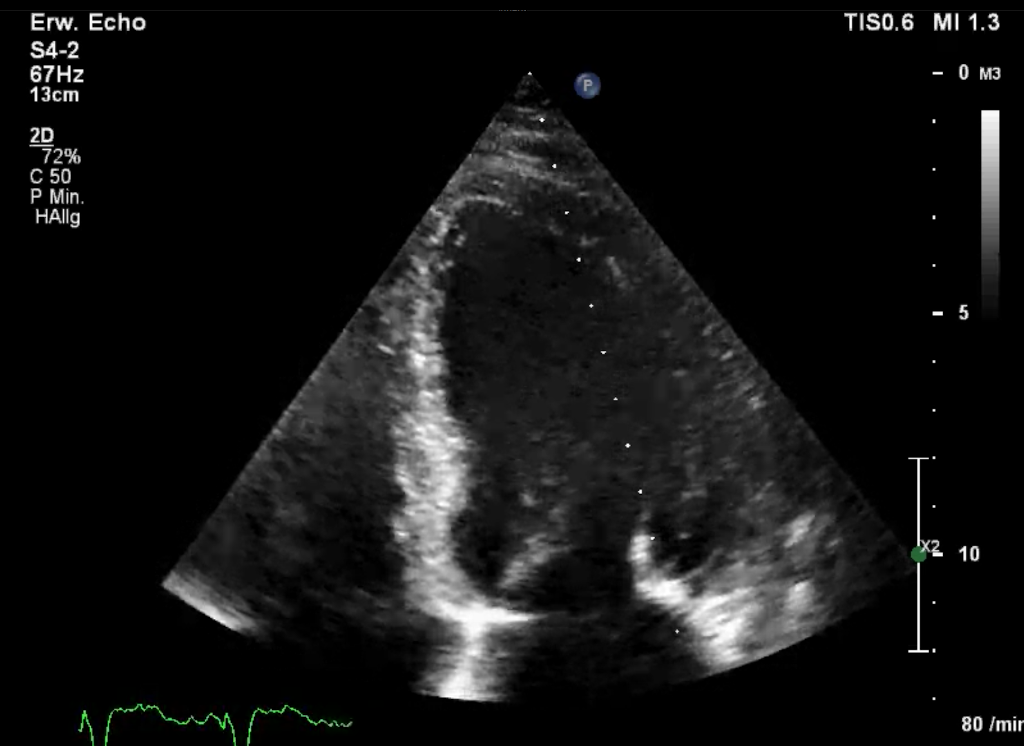

Edler-Echokardiographie

2D-Bild

2D-Bild (realtime)